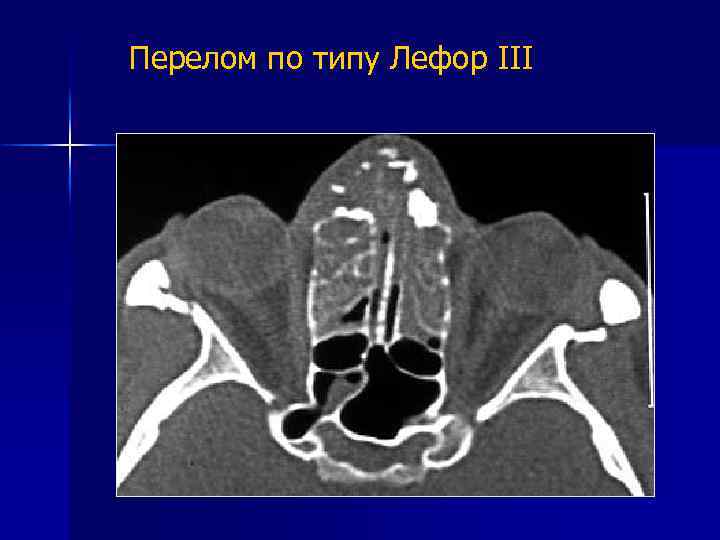

Перелом по типу Лефор III Костный фрагмент представлен верхней челюстью со скуловыми костями. Верхнечелюстная пазуха, скуловой отросток и подглазничный край не повреждены. В медиальном отделе линия перелома проходит аналогично 2 типу, а в латеральных отделах по лобно-скуловому шву и скуловой дуге.

Перелом по типу Лефор III